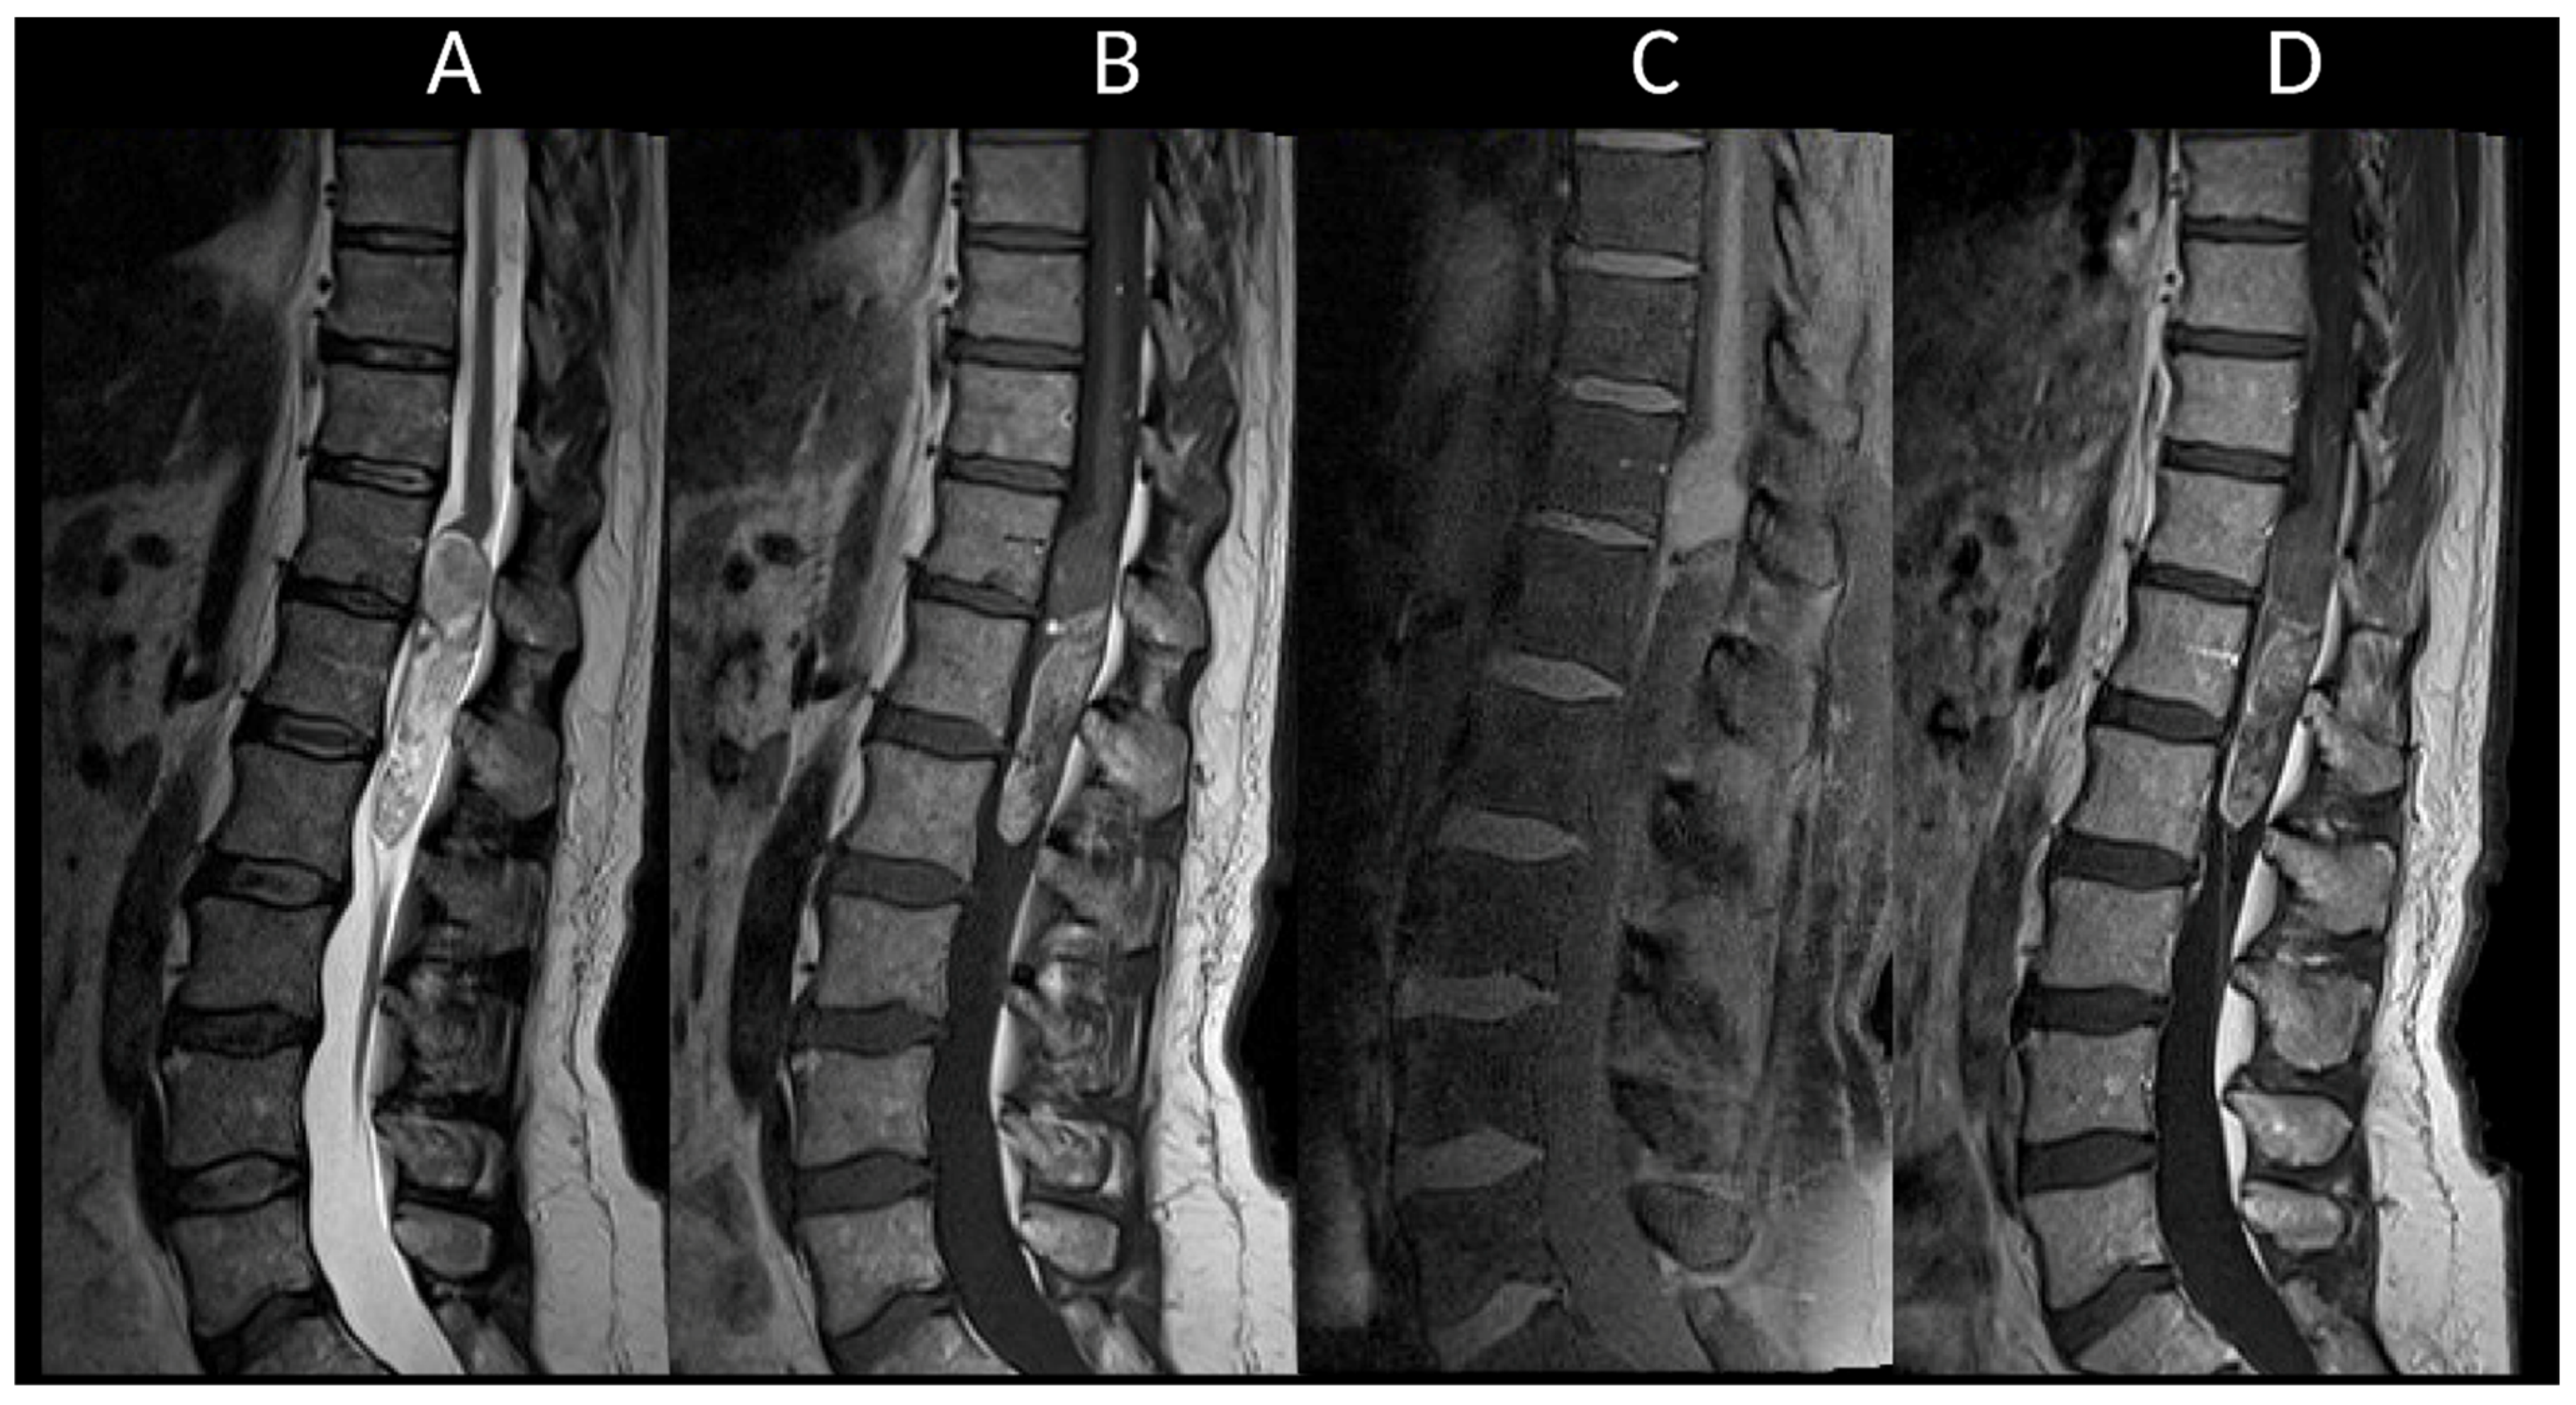

3.3.2. Spinal Dural Arteriovenous Fistula

3.3.3. Spinal Cavernous Malformation

- De Grado, A.; Manfredi, C.; Brugnera, A.; Groppo, E.; Valvassori, L.; Cencini, F.; Erbetta, A.; Ciceri, E.; Lerario, R.; Priori, A.; et al. Watch Brain Circulation in Unexplained Progressive Myelopathy: A Review of Cognard Type V Arterio-Venous Fistulas. Neurol. Sci. 2023, 44, 3457–3480. [Google Scholar] [CrossRef] [PubMed]

- Badhiwala, J.H.; Farrokhyar, F.; Alhazzani, W.; Yarascavitch, B.; Aref, M.; Algird, A.; Murty, N.; Kachur, E.; Cenic, A.; Reddy, K.; et al. Surgical Outcomes and Natural History of Intramedullary Spinal Cord Cavernous Malformations: A Single-Center Series and Meta-Analysis of Individual Patient Data: Clinic Article. J. Neurosurg. Spine 2014, 21, 662–676. [Google Scholar] [CrossRef] [PubMed]

- Saliou, G.; Krings, T. Vascular Diseases of the Spine. Handb. Clin. Neurol. 2016, 136, 707–716. [Google Scholar] [PubMed]